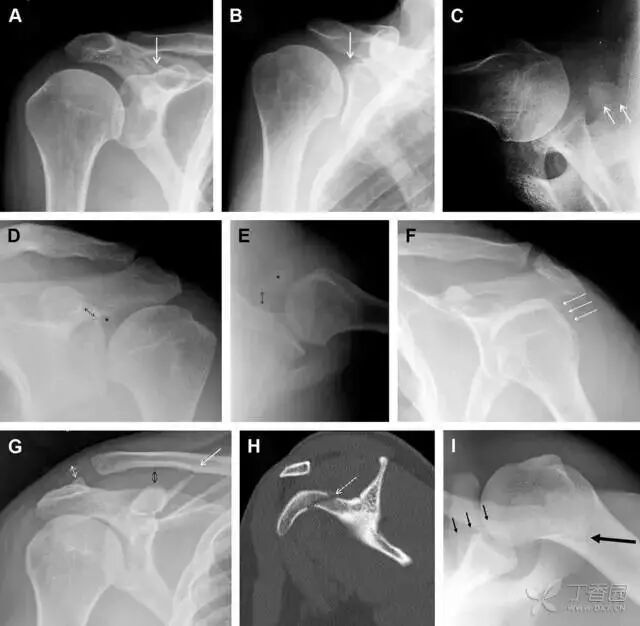

图 4 喙突骨折。66 岁男性患者,猎枪射击后右肩前方疼痛。(A)内旋位前后位片投影隐约可见喙突基底部骨折(白色箭头),(B)外旋位前后位片投影结构存在重叠,(C)腋位投影时可良好显示。(D~F)喙突骨折伴 Hill-Sachs 损伤:肩关节脱位后慢性疼痛,喙突骨折块(*)向前外侧移位(双箭头),在外旋前后位(D)及腋位(E)片上均可显示,在内旋位前后位(F)片上,喙突被遮挡,但可见肱骨头 Hill-Sachs 损伤。(G、H)喙突骨折伴肩锁关节脱位,肩锁关节分离(白色双箭头),而喙锁间距正常(黑色的双箭头),应警惕喙突骨折。(I)喙突与肩峰骨化中心:对于未成年人,喙突与肩峰骨化中心可同时存在,易与骨折混淆,此时,拍对侧的 X 线片对比将有助于诊断。

肩峰骨折

肩峰骨折为高能量损伤,多由直接暴力导致,好发于中青年患者,多伴有肩关节其它结构损伤。有必要拍摄 Rockwood 位(前后位片,X 线束尾倾),特别有利于显示肩峰下部及肩峰下间隙。

图 5 肩峰骨折。内旋位前后位(A)片上,骨折线几乎被喙突完全遮挡, 但是在标准前后位(B)和腋位(C)片上可见骨折线

骨折伴盂肱关节不稳

需要仔细评估肱骨头、大结节、关节盂边缘、肩峰、喙突等结构。典型的 X 线投射角度包括:内旋位前后位片、外旋位前后位片(Grashey 位)、侧位(肩胛骨 Y 位)、腋位片以及改良腋位片。

图 6 肩关节前脱位伴有 Hill–Sachs 和 Bankart 损伤:(A~C)肱骨头后外侧撞击骨折,白色箭头所示为骨折的内侧边界;(A)内旋位前后位片,(B)「V」形压缩骨折的下边界(虚线短箭头),(C)Garth 位(轴向投影)示 Hill–Sachs 损伤(虚线和实线折箭头),特别是对骨性 Bankart 损伤的诊断有帮助。(D、E)MRI 进一步证实了损伤

图 7 肩关节后脱位伴有反 Hill–Sachs 损伤。(A)外旋位前后位片可见一硬化带(黑箭头),此「凹槽征」与肱骨头关节面平行;(B)腋位片进一步证实了骨折的存在